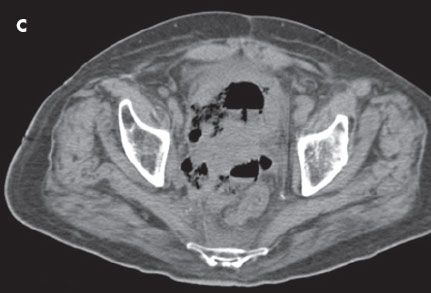

CT scans of the abdomen and pelvis showed a large prostatic mass without delineation between the prostate, rectum, and bladder. A fistula was noted between the rectum and bladder (A, B, and C). Copious subcutaneous gas was visible in the perineum and in all 3 corpora of the penis (D). Blood cultures were positive for Clostridium perfringens. Necrotizing fasciitis was diagnosed, and the patient underwent a loop colostomy.